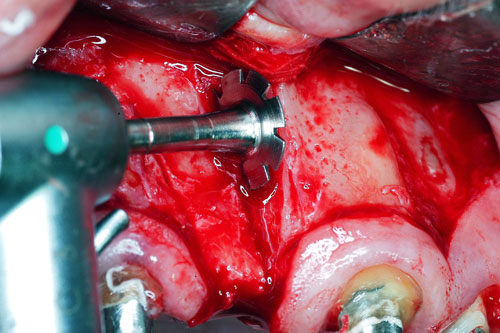

Mientras dichos movimientos ortopédicos se producen (período que supondrá otros seis meses), estudiamos los actos quirúrgicos a realizar en los cuatro implantes que pondremos. De acuerdo al estudio Desatascan realizado observamos tres situaciones diferentes: 1º-El Primer Molar Inferior Izquierdo, lo instalamos mediante Cirugía Minimamente Invasiva , con la aplicación de una Férula Quirúrgica Obtenida de los datos del scanner tratados con un programa de CMI (Cirugía Minimamente Invasiva), previa prueba en un modelo estereolitográfico, ya que la altura ósea era apenas de 9 mm. 2º- El Primer Molar Superior Derecho, se implantará mediante una ligera Elevación Atraumática (Trans alveolar) de Seno una vez logrado el espacio mesio distal necesario. 3º- El Incisivo Central Superior Derecho ausente, cuenta con un sustrato óseo prácticamente inexistente. El espesor de la tabla era de menos de 2 mm. Los caminos posibles a seguir para contar con una Rehabilitación de piezas independientes son dos: Optamos por esta segunda opción por ser menos cruenta y no necesitar de una zona dadora. Técnica esta que pondremos en práctica en dos etapas diferidas: 1º-Incisión horizontal palatinizada, incisiones peri rodetes gingivales e incisiones de descarga. Dilatación que comenzamos con dos incisiones de descarga sobre la cortical vestibular realizadas con disco. y el comienzo de la dilatación propiamente dicha mediante una hoja de bisturí, para luego seguir con un periostótomo . Recién después de alcanzada una cierta separación de la cortical vestibular de la palatina, empezamos con los dilatadores roscados. En este punto podríamos haber utilizado sin riesgos un Implante de 3,8 mm de diámetro, pero a fin de mejorar la estética del pilar emergente decidimos rellenar con material osteoconductor y osteoinductor (BiOss) y cubrir mediante membrana reabsorvible ( Bio Guide). 2º-Implantación seis meses después. Mientras se van cumpliendo los tiempos antes mencionados, y comprobamos reiteradamente la funcionalidad de la oclusión con los provisorios, tomamos impresiones definitivas y construimos primero el maxilar inferior, para definir en primer término la porción inferior de la Guía Anterior., y a nivel posterior Curvas y Microplanos. Para luego realizar los cuadrantes premolar- molar del superior: La espera de la regeneración ósea y sus tiempos pertinentes, más la espera de los tiempos de la implantación, nos obligaron a modificar las etapas del protocolo D.AT.O de manera de mantener la –D- mediante el sector superior de la GA. en provisorios, mientras fuimos resolviendo en forma definitiva los demás sectores. Ya pasados los meses necesarios para recrear un hueso adecuado en el área del Incisivo Superior Derecho, procedemos a resolver la implantación de dicha zona, observando que todo el esfuerzo dedicado al mismo había sido inútil, ya que la formación de hueso se produjo minimamente. Cuatro meses después tomamos impresiones del sector Antero Superior de la Guía Anterior, incluyendo el arrastre de un transfer . Seguimos modelando la encía con un nuevo juego de provisorios. Y se construye entonces el sector superior de la Guía Anterior. Se efectúa un control radiográfico a los 6 meses. Se ha intentado mostrar en esta Rehabilitación, que a pesar de las distintas circunstancias de cada paciente, siempre debemos tener en cuenta la necesidad de ejercer la DESOCLUSIÓN del caso como prioridad número uno, para luego perseguir la ALINEACIÓN TRIDIMENSIONAL de las arcadas y obtener así una OCLUSIÓN equilibrada. D.AT.O. ES EL PROTOCOLO QUE DEBEMOS SEGUIR EN TODA REHABILITACIÓN. BIBLIOGRAFÍA 1)William Mc Horris,B.S.,D.D.S. Oclusión. Con especial énfasis sobre :El rol funcional y parafuncional de los dientes anteriores. 2)Von Spee , Craff(Anatomista alemán, describió la curva de compensación de la articulación de molares y premolares).CURVA DE SPEE 1.89 3)Stuart,D.”Some aspects of the inervation teeth.”Procedings of Royal Society of Medicine.20:1675,19274)Muhleman,H. y Savdir,S”Tooth movility-its causes and significance”Journal of Periodontology ,36:153,Marzo ,Abril,1965. 4)Muhleman,H. Y Savdir,S”Toothmovility its causes and significance” Journal of Periodontology,36:153,marzo,abril,1965. 5-Oclusión y Diagnóstico en Rehabilitación Oral. 6-Anatomia Odontológica. 7-A contribution to the study of the movementes of the mandible. 8-Celenza F.W, Nadeskin J.F.,Oclusión.Situación actual. 9-D´Amico 10-Dawson P.E. 11-Huffman –Regenos. 12-Hobo S.-Takayama H.A. 13-Lucia V.O 14-Mc Horris. 15-Mc Horris. 16-Stuart C. 17-Vartan Veshnilian 18-Alvarez Cantoni H. AUTOR:Ratificación del Protocolo en Rehabilitación Bucal a pesar de las incidencias propias de cada caso clínico. A propósito de un caso.

Verificamos también el escaso ancho crestal, lo que nos obliga a utilizar dilatadores roscados y un osteótomo para elevar inicialmente la membrana de Schneider.

Elevación de membrana mediante periostótomo

Elevación de membrana mediante periostótomo